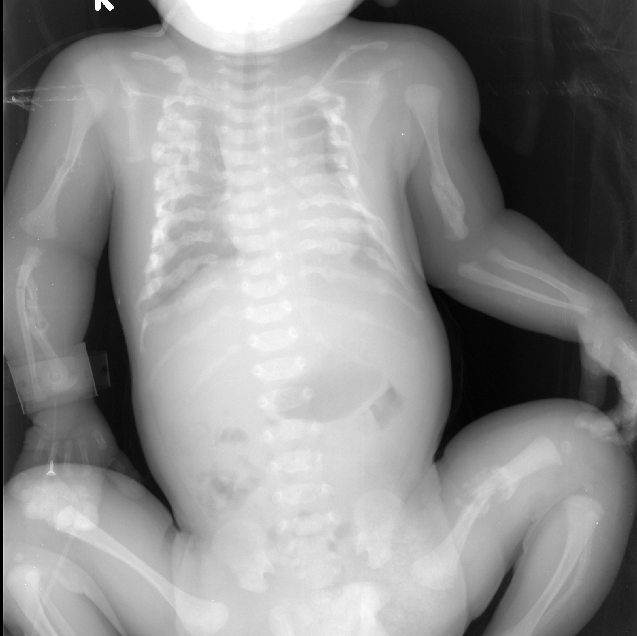

患兒X線片(多處骨折)

2014年的1231日凌晨434分本院新生兒科來了一位特殊的新生兒,患兒整個頭顱骨發(fā)育不良,觸及似棉絮狀又或似乎像剝了殼的雞蛋樣的腦袋,患兒左上肢活動可,肌張力稍差,右上肢無力(患兒X線片見尺橈骨骨折有關(guān)),不能抬高,也不能平移,雙下肢活動能力尚好。完善胸腹x線平片:雙側(cè)鎖骨中段、雙側(cè)多根肋骨、雙側(cè)肱骨中段、右側(cè)尺橈骨、左側(cè)股骨、左側(cè)腓骨中段骨折并部分骨折端骨痂形成。

患兒宮內(nèi)就出現(xiàn)全身上百處骨折,并見肋骨串珠及骨痂生長、頭顱骨發(fā)育不良,影像學診斷:先天性成骨不全,又稱脆骨病,屬稱瓷娃娃,是一種遺傳異質(zhì)性結(jié)締組織病。其特征為骨質(zhì)脆弱,是一種由于間充質(zhì)組織發(fā)育不全,膠原形成障礙而造成的先天性遺傳性疼痛。其主要缺陷是結(jié)締組織成分發(fā)育障礙,表現(xiàn)為骨、鞏膜、韌帶,甚至是主動脈瓣等膠原纖維發(fā)育不良。骨骼改變主要是成骨細胞減少,活力減低,骨樣組織生成不良,導致患者軟骨及下成骨障礙,骨小梁纖細而分散,骨皮質(zhì)菲薄,故易發(fā)生骨折。輕度在青春期前很少骨折,存活率較高;重度則可胎死宮內(nèi)。并發(fā)癥:由于患者長期臥床,可出現(xiàn)墜積性肺炎、泌尿系感染及褥瘡等并發(fā)癥。治療:無特效治療,原則是慎防骨折、盡量恢復活動度與功能。在治療過程中佩戴保護性措施,有效制動骨折端可愈合。目前針對此新生兒的患兒,主要加強護理:睡硬板床,患兒不能由母親抱于懷中哺乳,以免加重骨折,應由母親將奶擠出,裝入干凈的奶瓶中人工喂養(yǎng)。喂養(yǎng)時仍取頭高腳低位,頭偏向一側(cè),選擇合適的奶嘴,少量多次,謹慎喂養(yǎng),防止嗆奶窒息。詳細記錄奶量,保證營養(yǎng)供給。在為患兒進行各項操作時都應注意動作輕柔,各項操作集中進行,盡量減少搬動次數(shù)。行頭皮靜脈穿刺時固定手法宜輕,避免重壓,造成顱骨骨折。操作后保持患兒肢體處于功能位置。因本病無特效治療方法,且鈣劑、氟化物、維生素C等無療效,故大多數(shù)患者在圍產(chǎn)期、嬰兒早期或者1歲內(nèi)夭折。(新生兒 許春蓮)